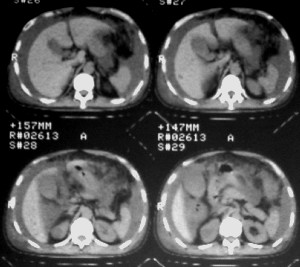

m ,60岁,右上肺ca术后一月。

右侧肺癌术后:肝内可见多个大小不等的低密度结节影。腹腔及双侧胸腔大量积液。考虑:肺癌并胸膜及肝脏转移。

纵隔淋巴结增大,双侧胸水。考虑术后残留,而非复发。

腹水,肝及右肾多发低密度影。考虑转移。

肝及右肾转移瘤,双侧胸水

右肾及肝内多发转移瘤,胸水。

1、右肺癌术后改变。2、双侧胸水、腹水。3、多发性肝囊肿,右侧肾囊肿。